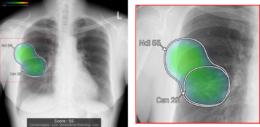

(3)所見名/スコア表示機能

従来のバージョンでは、複数の異常所見を検出した場合、検出された異常所見のうち最も確信度が高い所見のスコアのみを表示しており、各所見のスコアを確認したいという要望があった。新バージョンでは、各検出領域に対応する所見名と確信度を示すスコアを個別に表示できるようになった。これにより、医師は複数の異常所見について詳しい情報をひと目で把握でき、正確な診断を行うことが期待できる。

また、従来のバージョンでは、対象所見が重なった領域においてヒートマップが重なって表示されていた。そのため、異なる所見が混在している部分の識別が難しく、細かな判別や詳細な確認には限界があった。これに対し、新バージョンでは、対象所見が重なった領域についても、各所見ごとに独立した輪郭線を表示できるようになりなった。複数の異常所見が存在する箇所でも、それぞれの所見の範囲を明確に区別できるようになり、より詳細かつ正確な画像診断支援が期待される。